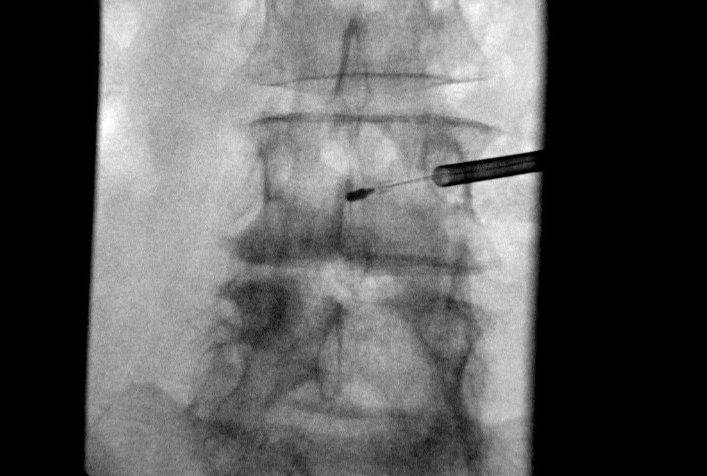

Doug Beall going over the top of screw

image_d763a6f2-305e-4d46-948b-68926a28257620220714_162000.jpg

image_b1888c74-3b51-4a67-af3a-4fc0d9216f5a20220714_161956.jpg

image_5c396b3d-57d1-4a7d-8f47-79217506a40e20220714_161954.jpg

image_c8082d3b-519b-4414-a67e-0560bf23415e20220714_161949.jpg